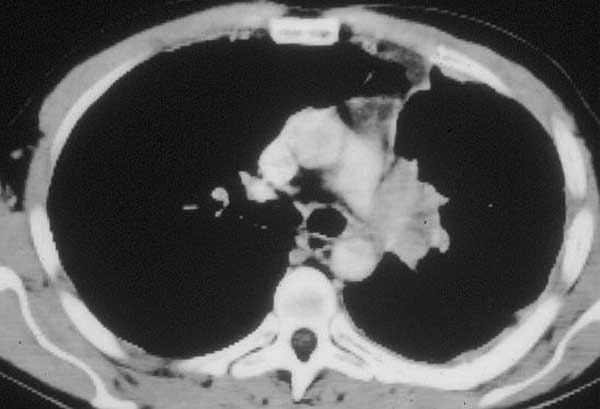

Infiltration of the PA on the right side requiring arterial reconstruction is less frequent. Partial resection of the PA often is performed in conjunction with right upper lobe sleeve resection (Figure 13). After right upper sleeve lobectomy en bloc with partial resection of the PA, the stump of the main bronchus and the PA defect are left open in the field (Figure 14). Harvesting of the pericardium is performed as above, based on the size of the portion of the resected pulmonary artery. Patch reconstruction of the PA is completed as above before reimplantation of the bronchus to reduce the arterial clamping time (Figure 15).

![]() |

On occasion a sleeve resection of the upper lobe and the pulmonary artery is necessary (Figure 16). Pulmonary artery and inferior pulmonary vein control are obtained as described above. The vascular conduit is constructed from a segment of autologous pericardium (Figure 17). When sizing the conduit, two points must be considered: the PA stumps can be approximated closer than it seems, and the conduit will stretch more than predicted. It is advisable to tailor the length of the conduit on the basis of the resected arterial segment, because the elasticity of the two tissues is comparable. The bronchial anastomosis is performed first to avoid traumatizing the PA (Figure 18). The PA is reconstructed by end-to-end anastomosis with running 5/0 or 6/0 monofilament suture (Figure 19).